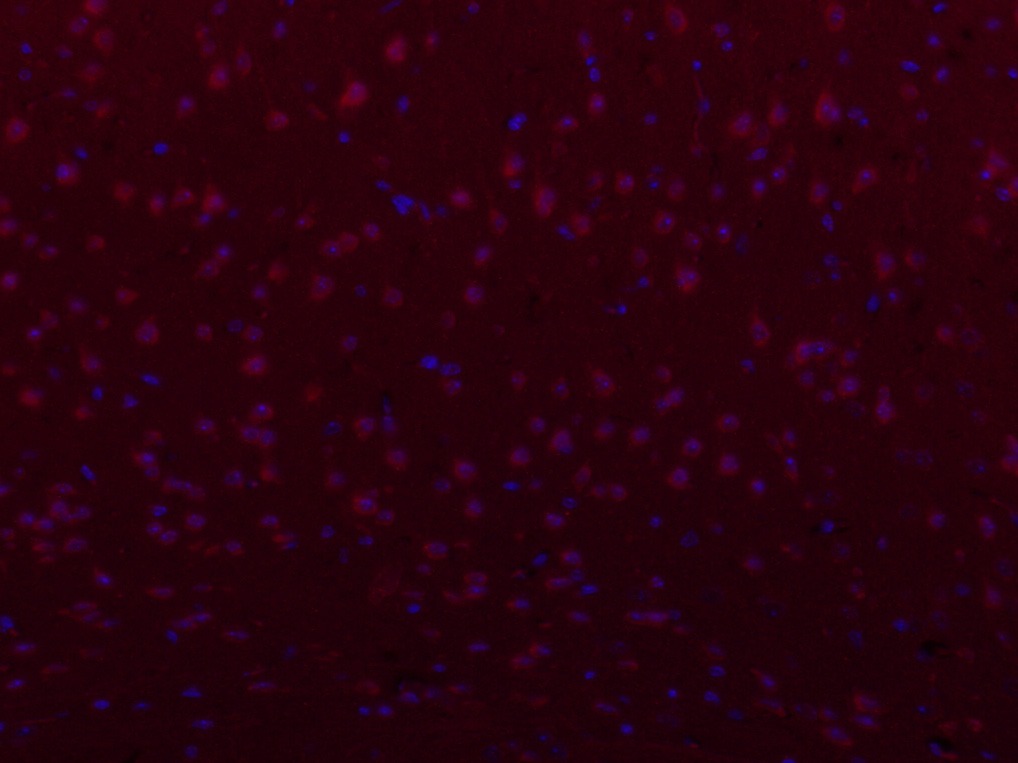

| Verified Activity | 1. Hela cell; 4% Paraformaldehyde-fixed; Triton X-100 at room temperature for 20 min; Blocking buffer (normal goat serum) at 37°C for 20 min; Antibody incubation with (PIEZO1) polyclonal Antibody, Unconjugated (TMAB-01536) 1:100, 90 minutes at 37°C; followed by a conjugated Goat Anti-Rabbit IgG antibody at 37°C for 90 minutes, DAPI (blue) was used to stain the cell nucleus. 2. Paraformaldehyde-fixed, paraffin embedded (Mouse brain); Antigen retrieval by boiling in sodium citrate buffer (pH6.0) for 15 min; Block endogenous peroxidase by 3% hydrogen peroxide for 20 min; Blocking buffer (normal goat serum) at 37°C for 30 min; Antibody incubation with (FAM38A) Polyclonal Antibody, Unconjugated (TMAB-01536) at 1:400 overnight at 4°C, followed by operating according to SP Kit (Rabbit) instructionsand DAB staining. 3. Paraformaldehyde-fixed, paraffin embedded (Mouse brain); Antigen retrieval by boiling in sodium citrate buffer (pH6.0) for 15 min; Block endogenous peroxidase by 3% hydrogen peroxide for 20 min; Blocking buffer (normal goat serum) at 37°C for 30 min; Antibody incubation with (FAM38A) Polyclonal Antibody, Unconjugated (TMAB-01536) at 1:400 overnight at 4°C, followed by a conjugated Goat Anti-Rabbit IgG antibody for 90 minutes, and DAPI for nucleus staining. ![]() ![]() ![]() |